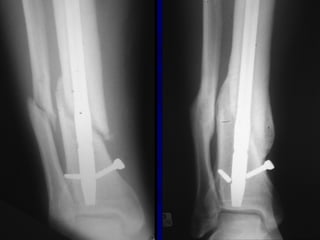

Expanded Indications • Proximal1/3 • Distal 1/3 • Increased Problems

• 53.

• Proximal Fractruesare technically more challenging • Prone to Valgus & • Pro-curvatum deformities

Technique • Screws placedon concave side of deformity.

Blocking (Poller) Screws •Functionally narrow im canal • Increase strength and rigidity of fixation

The Use ofPoller Screws as Blocking Screws in Stabilising Tibial Fractures Treated with Small Diameter Nails • 21 patients • All healed within 3-12 months • Mean alignment 1 degree valgus, antecurvatum 2 degrees. Krettek C, et al. JBJS 81B: 963, 1999

• Entry Sitefor Proximal fractures Critical • Reference is Lateral Tibial Spine

Proximal and DistalCases Courtesy of R. Winquist M.D. Seattle, Wa.